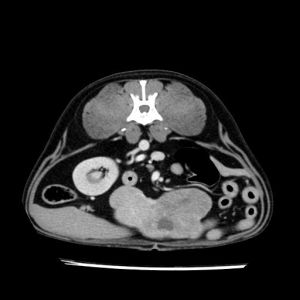

La lesione focale epatica , la ceus,la Tac e il chirurgo .